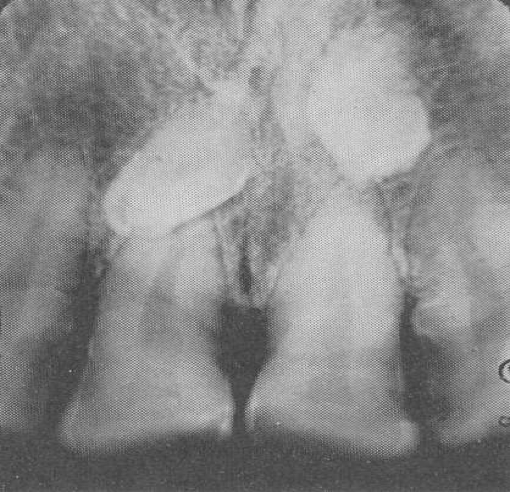

Hypercementosis

Excess cementum formation